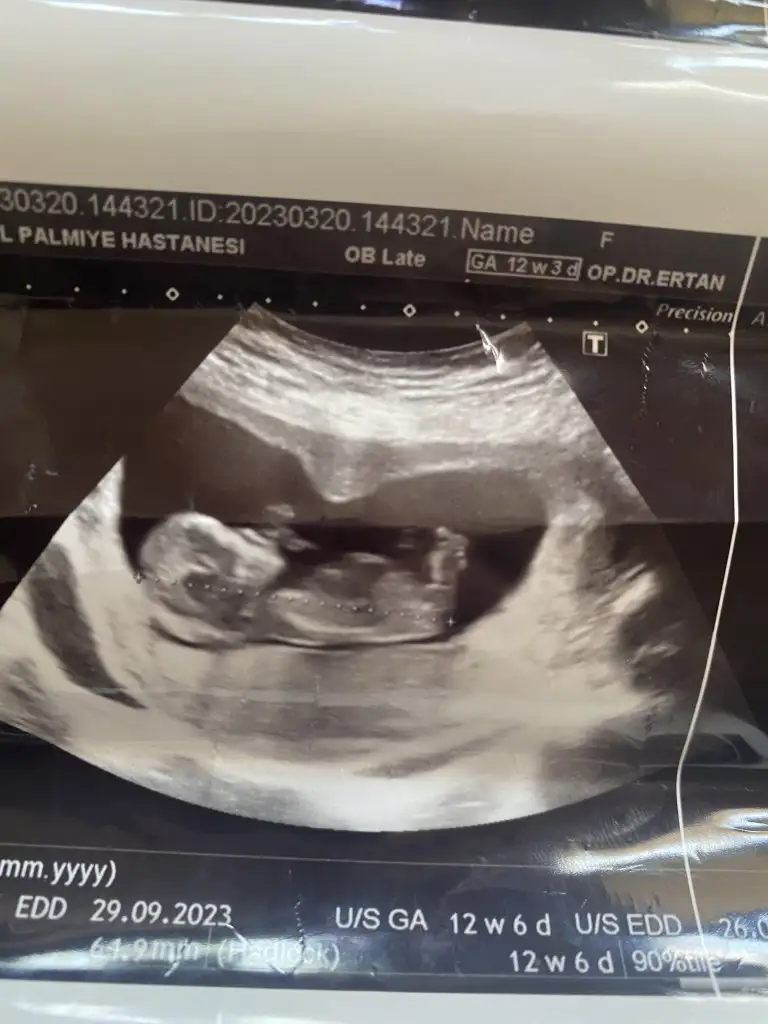

Merhaba ben bugün itibariyle 14 haftalık gebeyim. 11. Haftada perinatolog erken ama bebeğin erkeğe benziyor dedi. 12 de doktorum da aynı şeyi söyledi. Ama 12+4 de gittiğim ayrıntılı ultrasonda nub teorisine göre yüzde 70 kız dedi. Hatta biz erkeğe benzettiler deyince yok yok kız çoğunlukla da bu teori doğru çıkıyor dedi. Biz de kız dedik herkese. Bugün 14 hafta oldum kontrolümde kendi doğum uzmanım sırtı dönük ama bşr çıkıntı var kordon da olabilir erken ama ben erkek tahmin ediyorum dedi. Yine de kordonla karışabilir dedi. Artık iyice kafam karıştı. Sizin fikriniz ne? Benzer birşey yaşayan varsa paylaşır mısınız? Ultrason fotoğrafı bırakıyorum anlayan baksın lütfen.